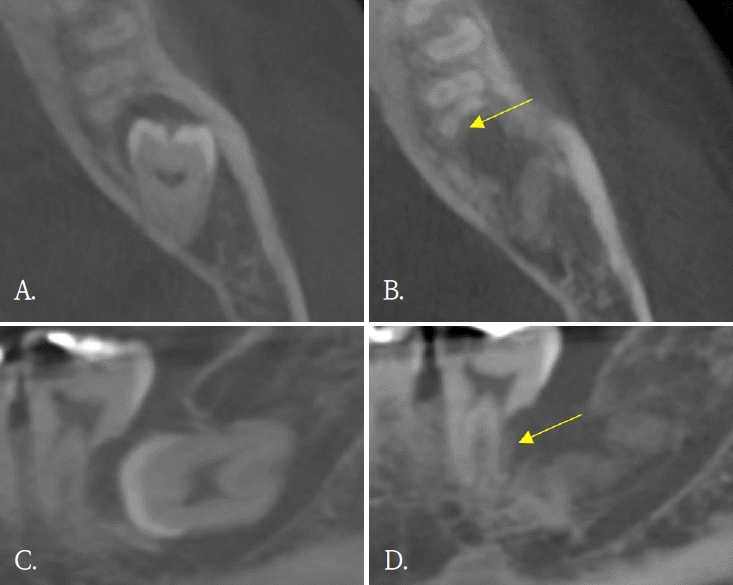

Figure 3.

Pulpal atrophy with apex closure is visible on postoperative panoramic radiography (yellow arrows). A. Pre-operative panoramic radiography. B. Panoramic radiography after 4 months of surgery.